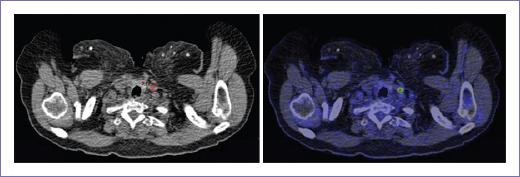

Figura 4 Metástasis ganglionar cervical hipermetabólica en paciente con antecedente de adenocarcinoma de recto, no visualizada por tomografía computarizada.

Se realizó también la evaluación de la estadificación N y M obtenida por PET-CT y TC, en la cual, por ambos métodos, se identificó solo un paciente N1A, la PET-CT identificó cinco pacientes N1B y tres pacientes N2A, mientras que la TC identificó cuatro y dos pacientes respectivamente; no se identificó afectación ganglionar en seis pacientes por PET-CT y ocho pacientes por TC (Fig. 5).

Figura 5 Metástasis en sacro derecho hipermetabólica en paciente con antecedente de adenocarcinoma de colon derecho, no visualizada por tomografía computarizada.